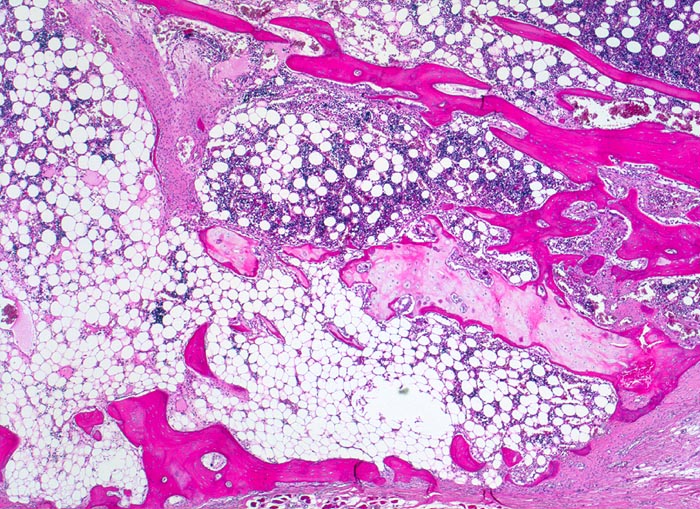

PathoPic – image database / PathoPic ID 5141 - Osteogenesis imperfecta: Frakturkallus

Osteogenesis imperfecta: Frakturkallus

Frakturkallus bestehend aus metaplastischem Bindegewebe, Knorpelgewebe und Knochengewebe.

Tod an Rechtsherzversagen bei Cor pulmonale. Multiple, zum Teil nicht ganz frische Frakturen vorwiegend der Rippen mit ausgeprägter Deformierung des Thorax und des übrigen Skeletts. Generalisierte Osteopenie. Kyphoskoliose. Multiple Knochenmarkembolien der Lunge.